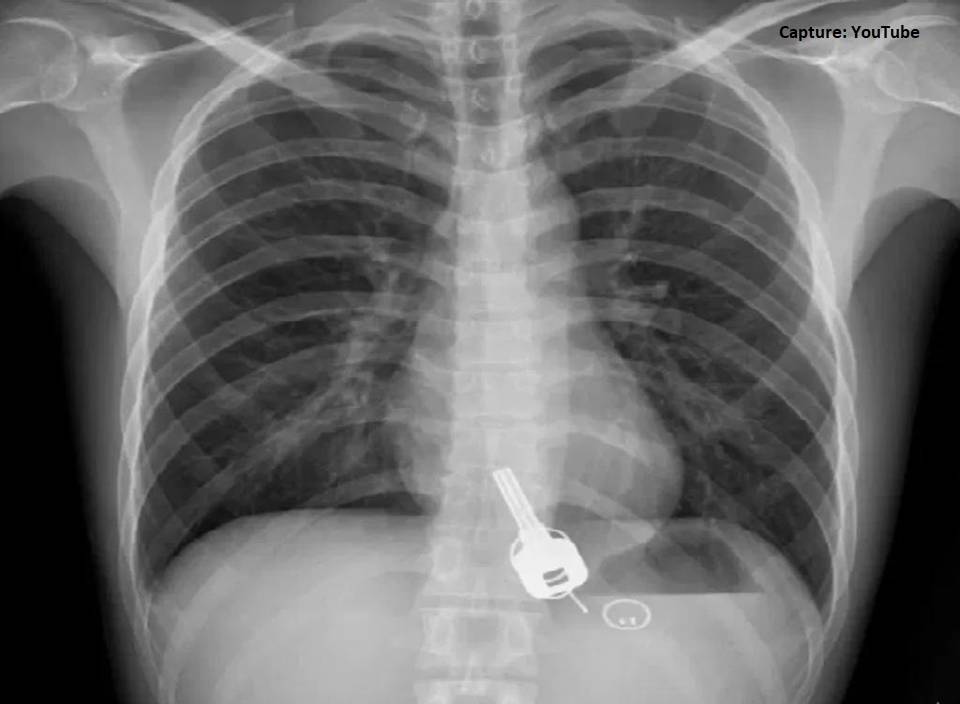

Pensando a lo mejor que se trataba de un infarto, el hombre acudió a la emergencia del Hospital Popular de Dongguan provincia de Guangdong, y adivinen qué. Después de varios análisis los médicos optaron por realizar una radiografía y una endoscopia, que revelaron nada más y nada menos que la existencia de un juego de llaves en el estómago del individuo. En el siguiente vídeo podrás observar algunas imágenes que obtuvieron los doctores.

Seguramente imaginaste que sería como el tema de los perritos, que cuando se comen algo que no deben lo expulsan en sus heces fecales, pero en este caso no fue así. Los médicos se dieron cuenta que las llaves estaban alojadas en el esófago del pobre hombre, por lo que determinaron que debían practicarle una cirugía con carácter de urgencia.